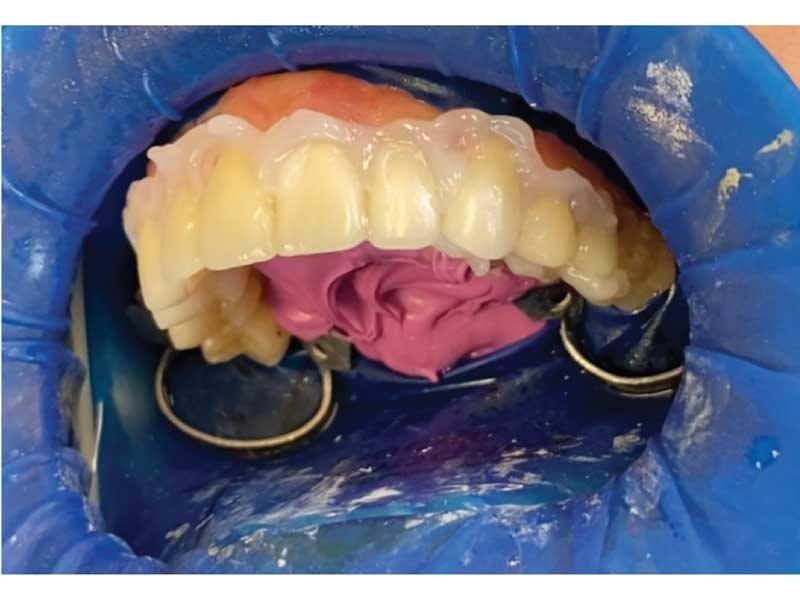

Lorraine drives six hours each way to see me, so I did her case all in one day: TENS bite; sectioned it; built up the lowers with resin to open the vertical (this is one of the cases I didn’t want to send out to a lab); prepped for 10 upper veneers (Fig. 24); temporized uppers; checked occlusion; and refined with TekScan. She came in with broken-down bonding and constant migraines, and left with beautiful temporaries and no more headaches. She came down a few weeks later to insert her gorgeous veneers (Fig. 25, thanks to Aurum Group) and I prepped, scanned, designed and milled and inserted her lower onlays to restore her lower teeth to her new vertical (Figs. 26–31). She has been pain-free ever since.

Dental Occlusion

Fig. 24

Fig. 25